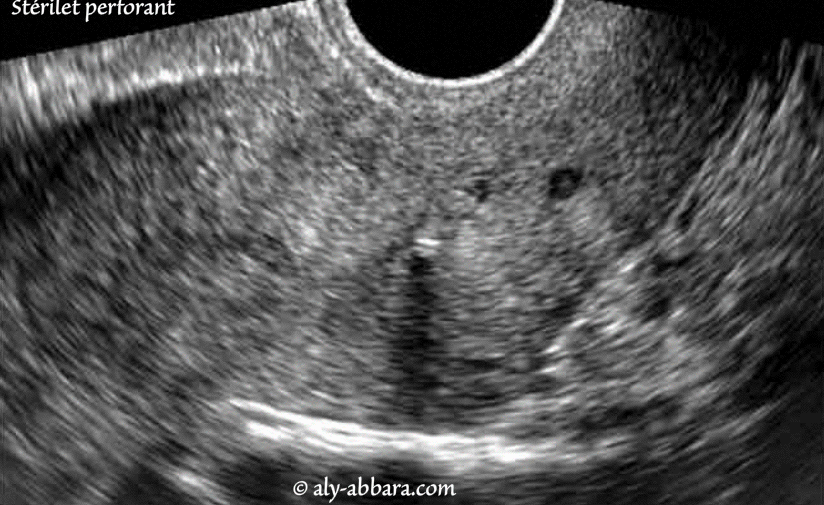

Celle-ci survient le plus souvent dans les suites immédiates de la pose mais "reste très rare", tempère la gynécologue. Dans de rares cas, il peut cependant arriver que ce contraceptif se déplace : soit vers le bas, ce qui correspond à une descente voire à une expulsion du dispositif, soit dans le corps suite à une perforation de l'utérus.

Si la perforation est passée inaperçue, le risque de grossesse est évidente d'où l'intérêt de ne passer à côté. Si la perforation est passée inaperçue, le risque de grossesse est évidente d'où l'intérêt de ne passer à côté. Pour éviter les risques de perforation de l'utérus et vérifier que le stérilet soit posé au bon endroit, le gynécologue va examiner la profondeur de l'utérus.

Diagnostics Free FullText Uterine Perforation as a Complication of the Intrauterine. Lorsque le stérilet se déplace dans un utérus fragilisé - par exemple par une grossesse, un accouchement, une fausse couche, une IVG ou une césarienne - il risque de perforer la paroi utérine et de migrer sous les côtes ou dans l'abdomen.Ce risque de perforation reste un événement très rare : il surviendrait dans 1. Si la perforation est passée inaperçue, le risque de grossesse est évidente d'où l'intérêt de ne passer à côté.